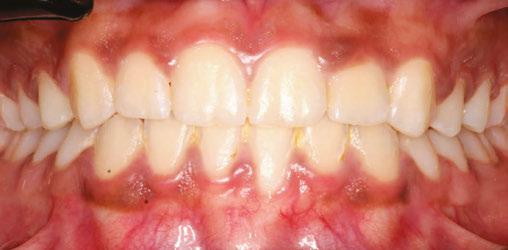

Figures 5A and 5B: Adolescent with anterior open bite: Orthognathic surgery unnecessary post-myofunctional therapy. 5A. Pre-myofunctional therapy: If mouth breathing is left untreated until the patient is skeletally mature, the only remaining way to correct the jaw discrepancy may be with orthognathic surgery. This patient was healthy and breathing through his nose until age 3 when he went to preschool. His colds and breathing issues did not clear until he was 7 years old. By then, he had a mouth breathing habit. Now at 17, he is in braces for the third time and being prepared for surgery to align his jaws. There are a number of myofunctional problems including lip incompetence, low forward tongue posture, and tongue thrust contributing to his severe open bite. 5B. Post-myofunctional therapy: His therapy included correcting his mouth breathing by strengthening the lips, exercising and training the tongue to rest sucked up on the palate, and retraining his swallowing patterns for saliva, food, and drinks. He was an excellent compliant patient which is necessary for successful therapy. After 7 months of myofunctional therapy, his bite corrected without surgery because of the myofuctional therapy. The oral surgeon cancelled the surgery, and he had a successful orthodontic result because: 1) the mouth breathing was corrected; 2) the tongue thrust was corrected